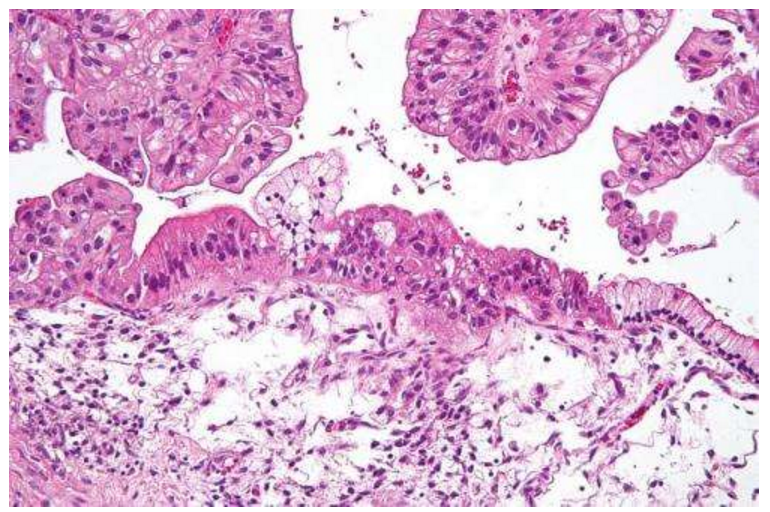

卵巢癌临床试验,康方生物AK112临床试验招募标准【部分纳入标准】1、入组时年龄 ≥ 18 周岁,≤ 75 周岁,女性。2、东部肿瘤协作组织(ECOG)体能状况评分为 0 或 1。3、预期生存期 ≥ 3 个月。4、受试者为经组织学或细胞学确诊的上皮性卵巢癌、输卵管癌或原发性腹膜癌。Ⅰb 期的受试者包括铂 敏感复发的患者(铂敏感复发定义为受试者末线接受含铂方案